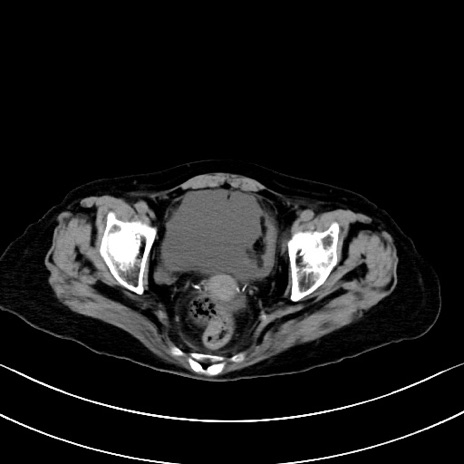

横断像

他院CT